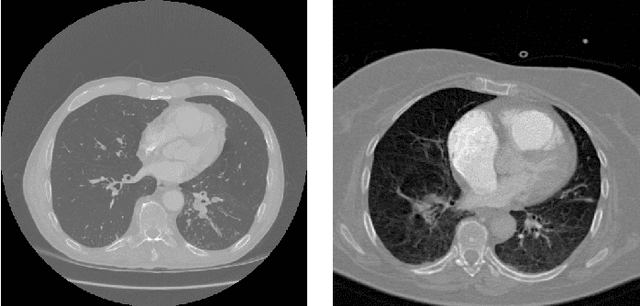

Abstract:Analysis of cancer and other pathological diseases, like the interstitial lung diseases (ILDs), is usually possible through Computed Tomography (CT) scans. To aid this, a preprocessing step of segmentation is performed to reduce the area to be analyzed, segmenting the lungs and removing unimportant regions. Generally, complex methods are developed to extract the lung region, also using hand-made feature extractors to enhance segmentation. With the popularity of deep learning techniques and its automated feature learning, we propose a lung segmentation approach using fully convolutional networks (FCNs) combined with fully connected conditional random fields (CRF), employed in many state-of-the-art segmentation works. Aiming to develop a generalized approach, the publicly available datasets from University Hospitals of Geneva (HUG) and VESSEL12 challenge were studied, including many healthy and pathological CT scans for evaluation. Experiments using the dataset individually, its trained model on the other dataset and a combination of both datasets were employed. Dice scores of $98.67\%\pm0.94\%$ for the HUG-ILD dataset and $99.19\%\pm0.37\%$ for the VESSEL12 dataset were achieved, outperforming works in the former and obtaining similar state-of-the-art results in the latter dataset, showing the capability in using deep learning approaches.